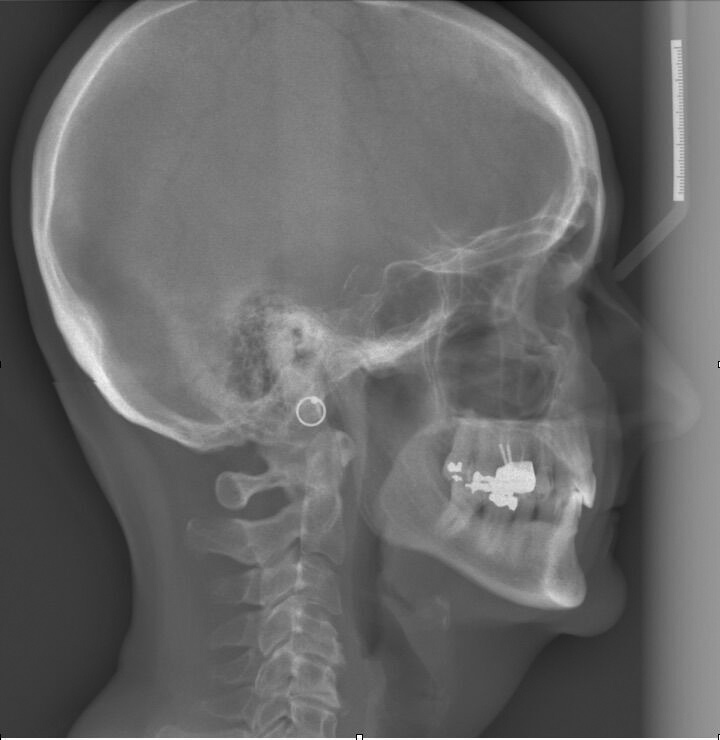

Dental sleep medicine (DSM) is a field in dentistry dedicated to the use and research of oral appliance therapy for the management of snoring and OSA. Oral appliance therapy is a noninvasive alternative to PAP therapy. Oral appliances fabricated by dentists with training in dental sleep medicine are commonly used to reposition the lower jaw forward to increase upper airway patency. Dental professionals have been recognized as being part of the multidisciplinary therapeutic team for the management of OSA because of their prime position of constant examination of the oropharyngeal areas. There are several oropharyngeal features contributing to the development of a narrow upper airway. These features are easily identifiable during a routine dental appointment, such as a large and scalloped tongue (Figure 1), narrow maxilla (Figure 2), small mandible (Figure 3), and retrognathic mandible (Figure 4). Combining clinical history intake, oropharyngeal examination, and the use of validated screening questionnaires, such as the STOP-Bang, dentists can screen for signs and symptoms of OSA and make recommendations for further diagnostic testing.

(4.) Lateral x-ray showing a retrognathic and entrapped mandible.

Figure 4